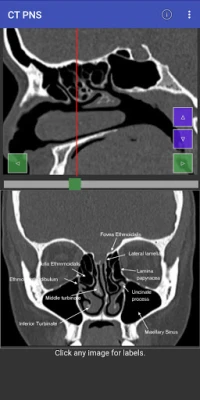

Domin sauƙaƙa fahimtar tsarin jikin ɗan adam ta hanyar hotunan CT scan, mun haɗa abubuwan ciki a matakai biyu (planes). Ɗaya daga ciki yana aiki a matsayin jagora (reference) wanda zai taimaka wajen fahimtar ɗayan sosai. Wannan hanya tana sa fahimtar tsarin jikin ya zama mai sauƙi da inganci, kamar yadda ake fuskanta a yanayin asibiti na gaskiya. Bugu da ƙari, za a iya gungurawa (scrolled) kowane mataki daban-daban, wanda hakan ke ba da damar fahimtar zurfin kowane sashi da cikakkun bayanansa cikin sauƙi.